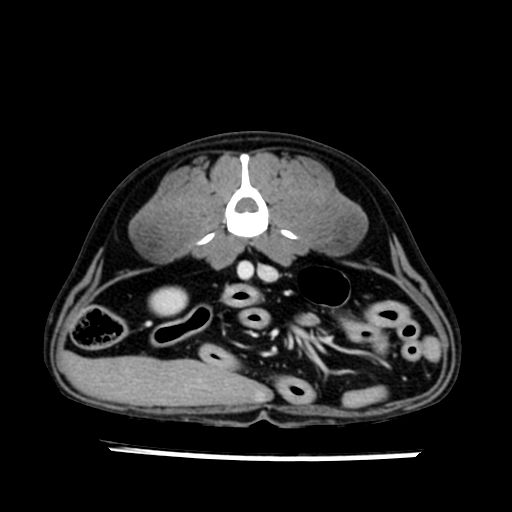

prescritto esame TAC

sequenza immagini limitata al fegato reni e surreni

le immagini ecografiche rispetto alla tac datano circa 7 mesi prima ,le surrenali sono normali nonostante il test acth sia risultato positivo .all’esame TAC dopo diversi mesi risultano aumentate armonicamente nel volume e si individua un forte sospetto di adenoma ipofisario .

sospetto adenoma ipofisario vs. meno probabilmente meningioma della base; intertiziopatia polmonare; lesione espansiva epatica, verosimilmente del lobo laterale sinistro, di sospetta natura neoplastica; lesioni spleniche di natura da definire; iperplasia/ipertrofia delle ghiandole surrenali, bilateralmente; vertebra di transizione del rachide toracico; tenosinovite cronica del muscolo bicipite brachiale di destra.